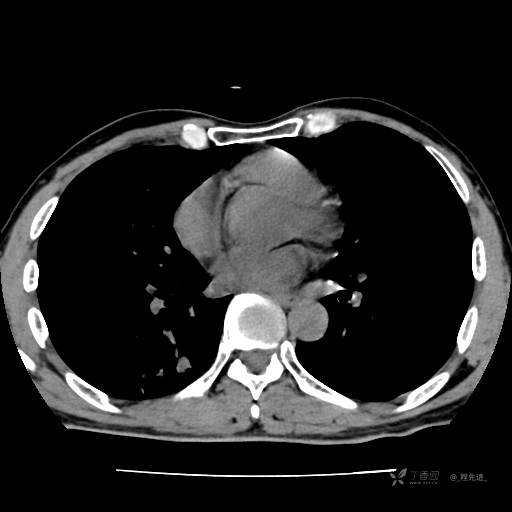

2月特别精彩病例|咳嗽、咳痰20余天,典型病例分享【结果已公布】

患者年龄:51岁

主诉:咳嗽、咳痰20余天

简要病史:20余天前开始出现咳嗽、咳痰症状,阵发性刺激性咳,白色粘痰,不易咳出,无发热,无咯血,无恶心、呕吐等不适,未诊治,咳嗽、咳痰症状持续存在。

体格检查:T:36.3 ℃ P:79 次/分 R:20 次/分 BP:128/64 mmHg,神志清楚,呼吸平稳,双肺呼吸音粗,右下肺闻及细湿性啰音。心率79次/分,节律整齐,各瓣膜听诊区未闻及病理性杂音。腹部未见异常,双下肢无水肿。

辅助检查:我院门诊胸部CT示:如下。心电图:窦性心律;正常心电图。